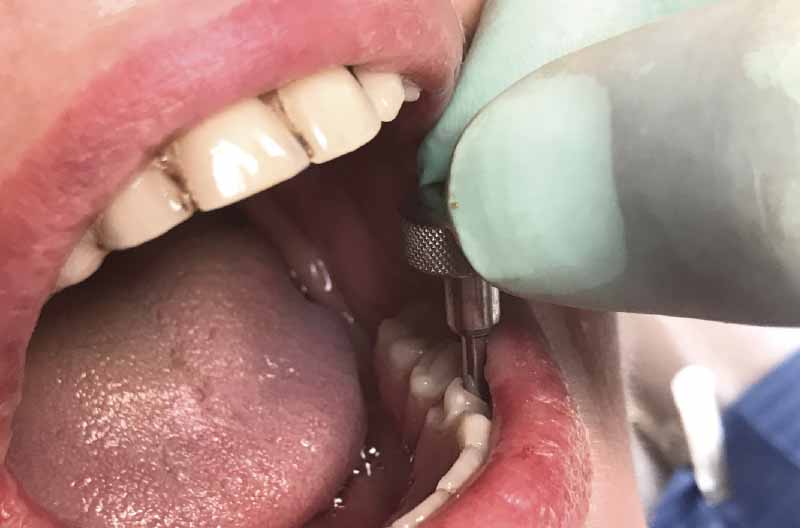

Per posizionare la dima chirurgica per la tecnica All-on-Four realizzo in zona mediana un foro con un diametro di 1,2 mm e una lunghezza di 10 mm (Figg. 14, 15). Le tacche verticali presenti sulla dima chirurgica All-on-Four, distanziate tra loro 7 mm, aiutano a dare la corretta inclinazione agli impianti distali, che sono i primi ad essere inseriti: posizionando la fresa sulla diagonale tra due tacche consecutive si ottiene un’inclinazione di circa 30°.

- Fig. 14

- Fig. 15